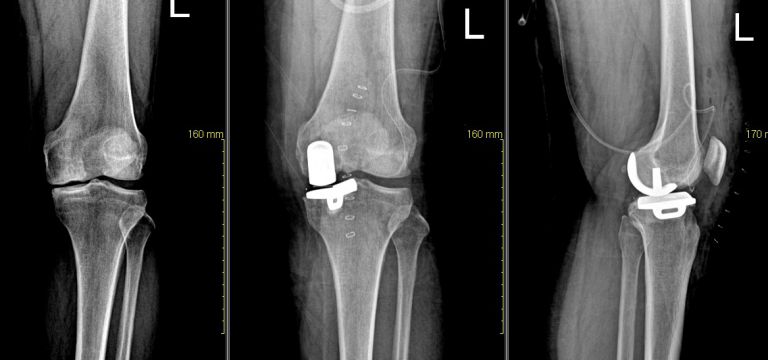

무릎 부분 인공 관절

관리자

| 2009.01.21

| 1873